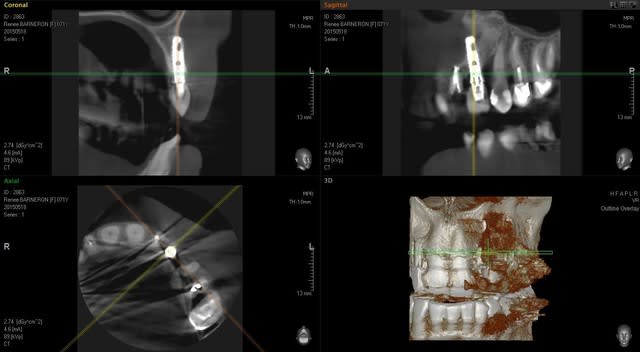

En 23 on a un implant qui semble bien ostéo intégré même si on remarque une forte perte osseuse sur la 24 mesial qui vient contaminer l'implant.

L'autre problème est que le cone bean révèle que l implant est en dehors de la crête osseuse

Il n'y a pas d'épaisseur pour poser un implant en 22 sans envisager une greffe au préalable.

Que faire de l'implant 23 ?

Pensez vous qu' il vaut mieux le laisser en place même si la greffe va forcément être en rapport avec son apex?

j'avais pas vu le scan de la 23

pas d'extension!!!